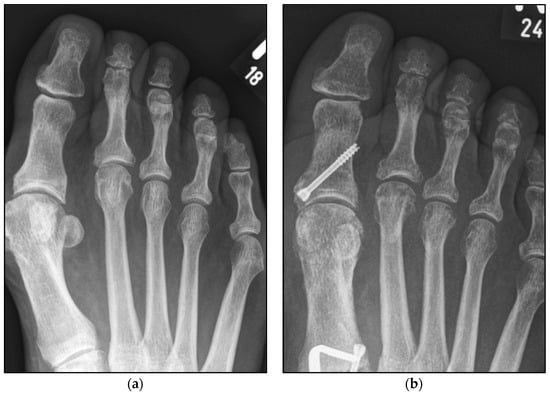

Figure 1.

Pre- and postoperative radiographic results of combined hallux valgus surgery and Weil osteotomy of metatarsal 2 and 3 (group A with screw), left foot. (a) Weight-bearing radiograph: anteroposterior view preoperative, (b) weight-bearing radiograph: anteroposterior view, 6 weeks postoperative.